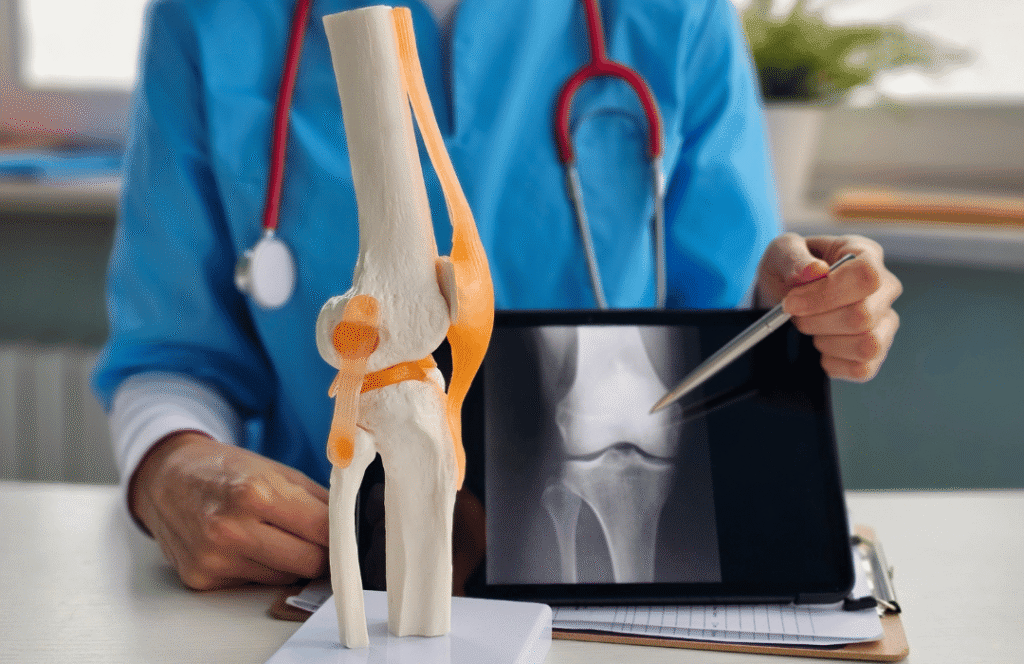

Specialist Doctor (Cardiology / Diabetes / Ortho)

Challenge

No personal brand and poor digital reach.

Solution

Personal branding, healthcare content marketing, and AI-based patient engagement.

Results

✔ Strong doctor brand authority

✔ Increased online consultations

✔ Improved patient retention